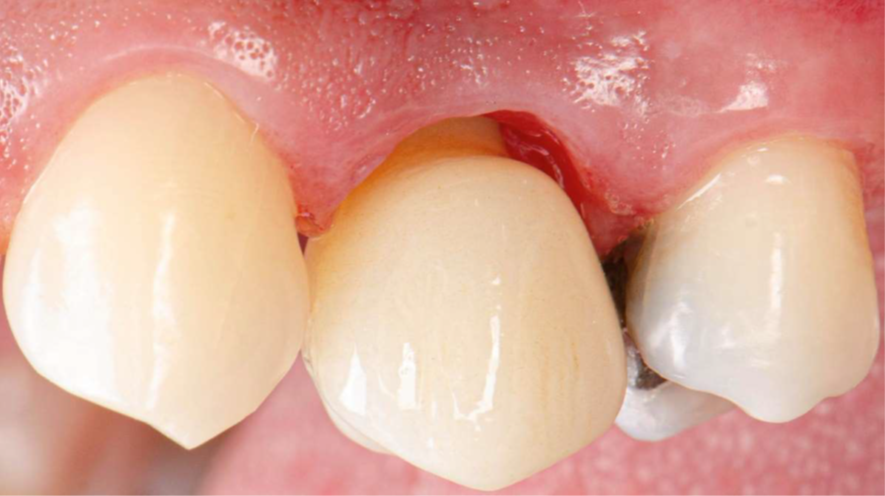

Neste caso relatado a seguir, a fratura do dente 24 levou à indicação de extração atraumática e implante imediato, com uso de biomateriais modernos e fluxo digital completo. O protocolo incluiu implante Due Cone (Implacil Osstem), preenchimento do GAP com Extra Graft, instalação do pilar Ideale definitivo (One Step One Abutment) e posterior coroa em zircônia monolítica.

Após a exodontia do elemento 24 com preservação das paredes ósseas, o preparo foi realizadoseguindo sequência de fresas recomendada para o implante Due Cone, cuja macrogeometriacônica e conexão Morse favorecem alto torque e retenção apical, condições desejáveis para oimplante imediato. A superfície jateada e atacada ao ácido intensifica a adesão celular inicial,contribuindo para osseointegração mais eficiente.

Confirmada a estabilidade primária por meio de ISQ acima de 70, prosseguiu-se com a instalação do provisório previamente confeccionado em impressão 3D. O modelo incluía aletas de captura para apoio nos dentes 23 e 25, garantindo estabilização inicial. Sobre o pilar Ideale, posicionou-se coifa metálica provisória, e então realizou-se a captura com resina flow, unindo o provisório impresso ao componente. Após fotopolimerização completa, a peça foi removida integralmente, permitindo acabamento extrabucal com precisão.

Nesse momento, as aletas foram removidas e o contorno foi refinado estrategicamente, respeitando zonas críticas e subcríticas do perfil de emergência, garantindo um provisório com selamento adequado do alvéolo enxertado, suporte papilar e manutenção do arquétipo gengival. O provisório finalizado foi reposicionado e colocado em função imediata. A partir daí, entra em cena a mecanotransdução: microcargas funcionais controladas atuam como estímulos biomecânicos capazes de converter forças mastigatórias em respostas celulares osteogênicas, incentivando deposição óssea, contato osso-implante e maturação do tecido peri-implantar. Em Implantodontia contemporânea, provisório não é apenas estética — é ferramenta biológica ativa que direciona cicatrização, protege o enxerto e constrói o perfil gengival definitivo.